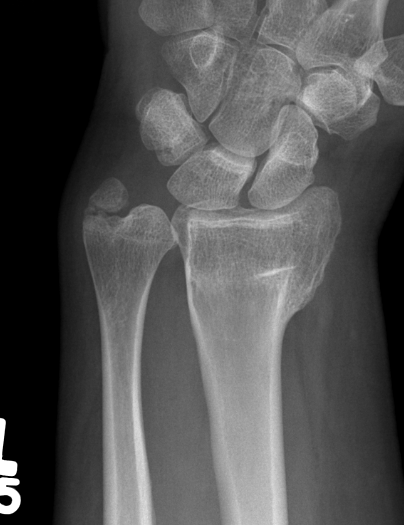

Malunion

| Radial shortening | Radial inclination | Positive ulna variance |

| Dorsal tilt > 15 degrees | Volar tilt > 10 degrees | Articular step > 3 mm |

Pathology

Radial shortening

- affects normal kinematics of the DRUJ

- ulnocarpal abutment

Dorsal tilt

- loss of flexion

- +/- midcarpal instability - DISI / CIND without interosseous ligament disruption

Xray

Bilateral xrays

PA film in neutral

- wrist neutral

- elbow & shoulder at 90°